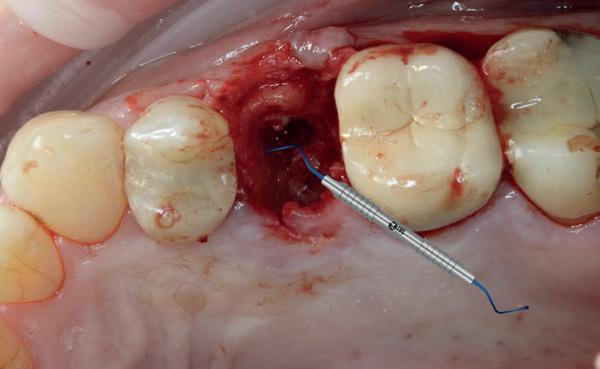

1. Afgebroken 24. Geen hoektandgeleiding aanwezig.

2. Decapiteren van het element en splitsen van de wortels.

3. Verwijderen van de radices.

4. Curettage en spoelen met een zoutoplossing.

5. Het ridge preservation protocol waarbij we proberen zoveel moge-

lijk bot te behouden met behulp van een xenograft.

6. De tijdelijke pontic, waarbij gebruikgemaakt wordt van de eigen afgebroken kroon en wat composiet. 7-10. Een full thickness flap osteotomie met hand plaatsing van een MegaGen AnyRidge Implantaat volgens protocol resulteerde in een

De implantaatplaatsing en de beslissende fout (afbeelding 1-13)

De extractie verliep voorspoedig, waarbij ik zoals al-

primaire stabiliteit van 60 Ncm.

11. Röntgenfoto ter controle van de plaatsing en de angulaire. Dit bone-level implantaat werd 4 mm onder de weke delen geplaatst.

12. Direct post-op. Een direct geplaatste tijdelijke kroon. Vastgezet met een torque van 20 Ncm en gehecht met prolene 5/0.

tijd probeerde de buccale botlamel intact te houden. Dit is cruciaal voor latere botbehoud en implantaatplaatsing. Na curettage en spoelen van de alveole beoordeelde ik de situatie opnieuw: de botcondities leken gunstig voor een immediaat implantaat.

Hier begon echter de cruciale fout in mijn klinisch besluitvormingsproces. In mijn streven naar maximale primaire stabiliteit - wetende dat immediaat belasten enkel mogelijk is bij hoge stabiliteit -on-

13. Röntgenfoto ter controle van de pasvorm van de direct geplaatste tijdelijke kroon.

derprepareerde ik de osteotomie. Dit betekende dat ik een iets te smal implantaatbed creëerde, in de hoop dat het implantaat stevig in het bot verankerd zou worden.

Op papier leek dit een logische stap: het MegaGen AnyRidge-implantaat dat ik koos, gaf me een stabiliteit van 60Ncm—een cijfer dat vertrouwen gaf in immediaat belasten. Maar in mijn enthousiasme had ik onvoldoende rekening gehouden met de biologische gevolgen van overmatige compressie.

Door de te hoge druk op het omringende bot verminderde daarin de doorbloeding, wat leidde tot een verhoogd risico op botnecrose. Dit was geen fout van abutmentkeuze of occlusie; dit was puur het gevolg van mijn drang naar optimale stabiliteit en de wens om het implantaat direct te belasten, onder invloed van patiëntdruk.